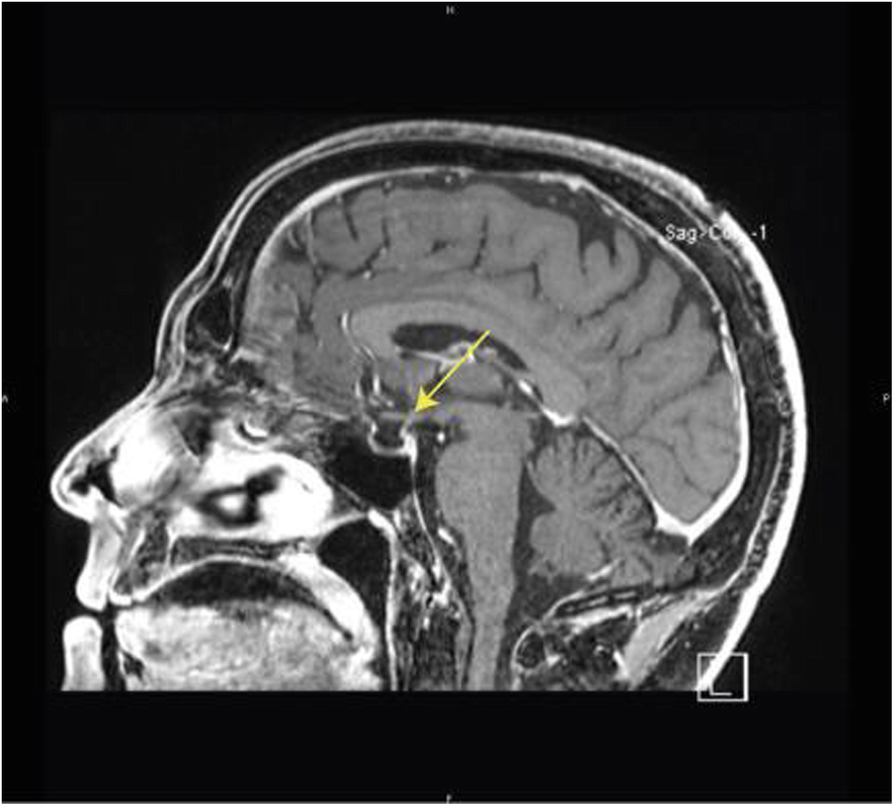

Fig. 1 (abstract P717).From: 34th Annual Meeting & Pre-Conference Programs of the Society for Immunotherapy of Cancer (SITC 2019): part 2Brain RMNBack to article page